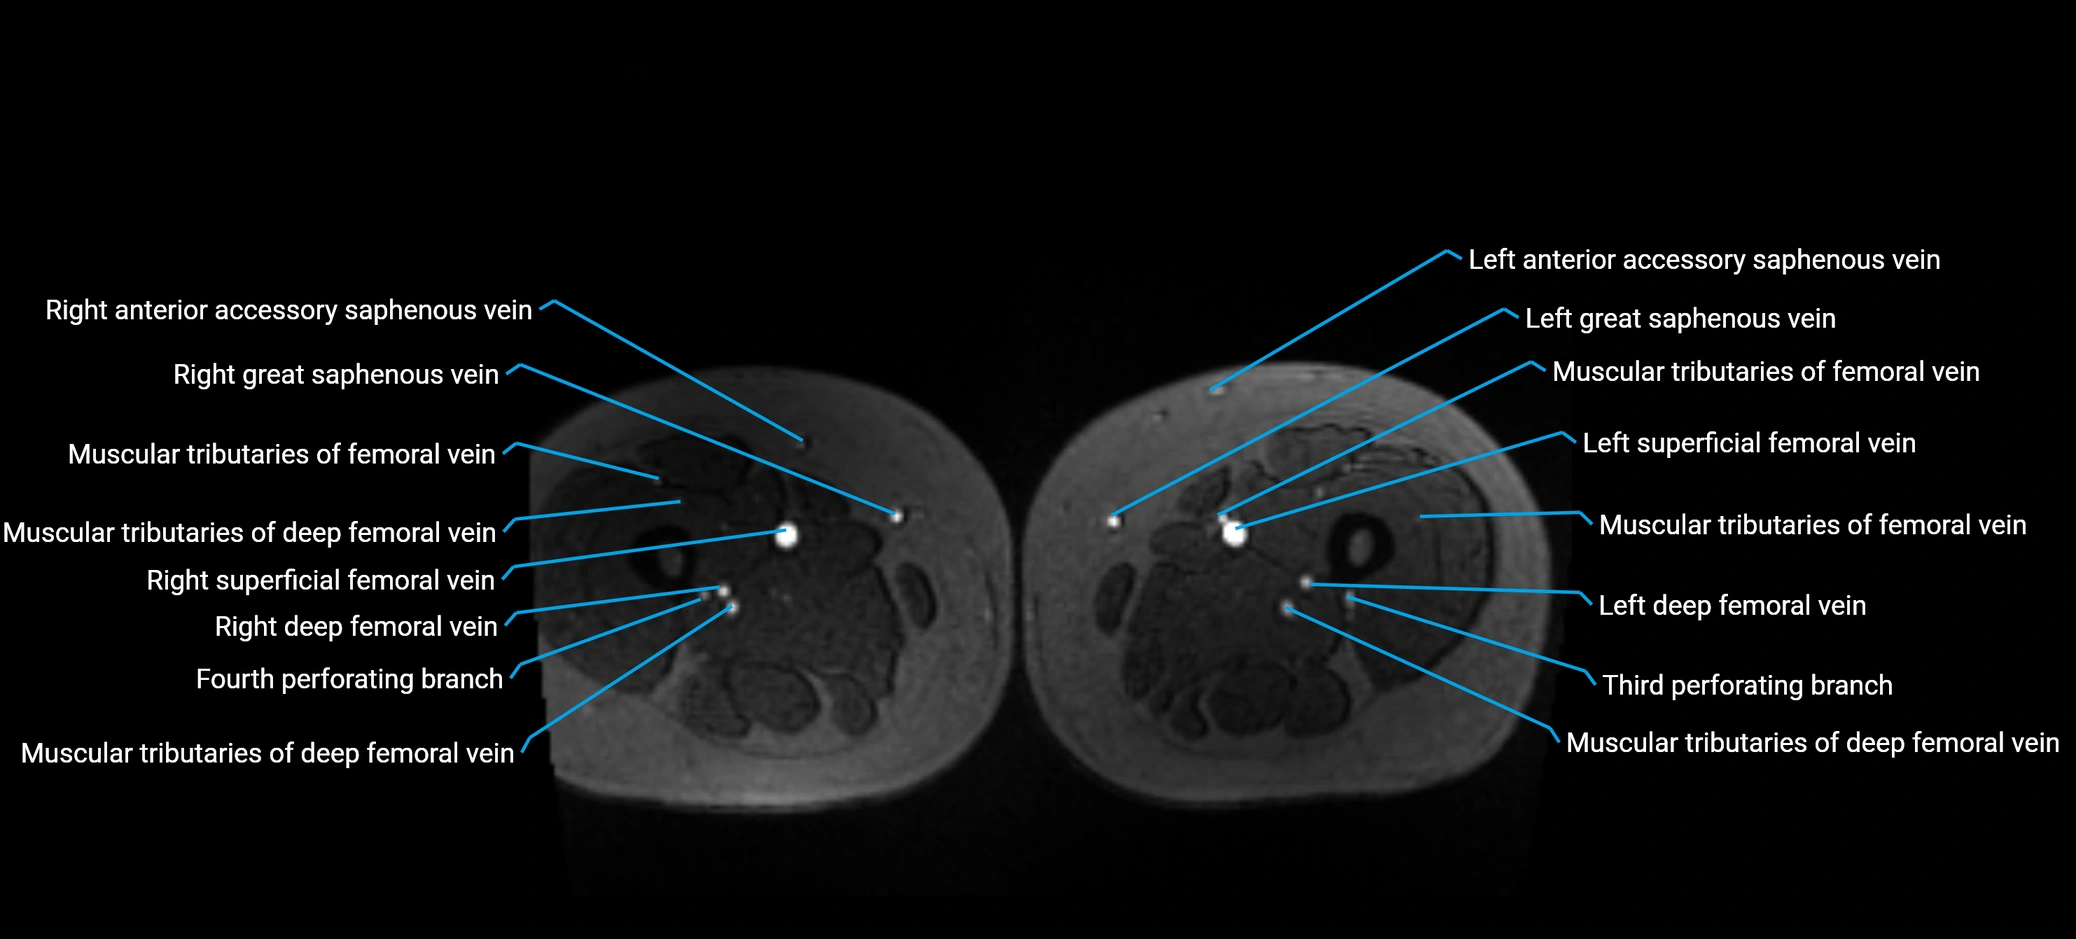

MRI image

image